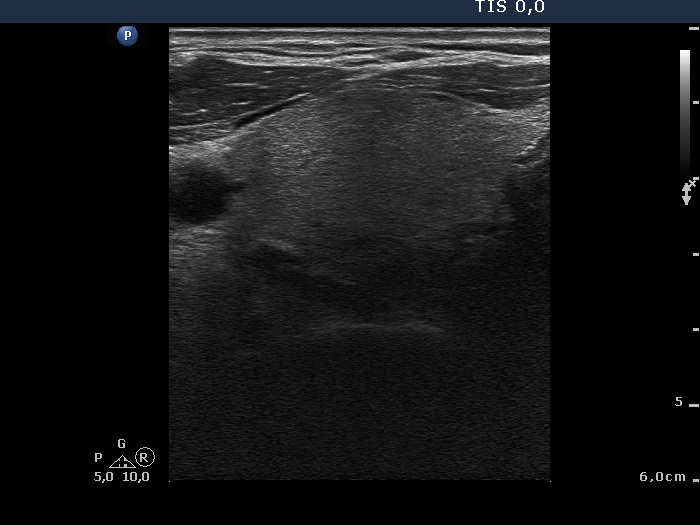

Ultrasonography: The thyroid was echonormal with a few insignificant lesions. There was a large cystic lesion dorsal to the lower third of the right lobe.

After aspiration of 10 ml yellow fluid the size of the lesion decreased from 35x31x42 mm to 29x22x39 mm. The patient refused to aspirate more fluid because her complaints ended.